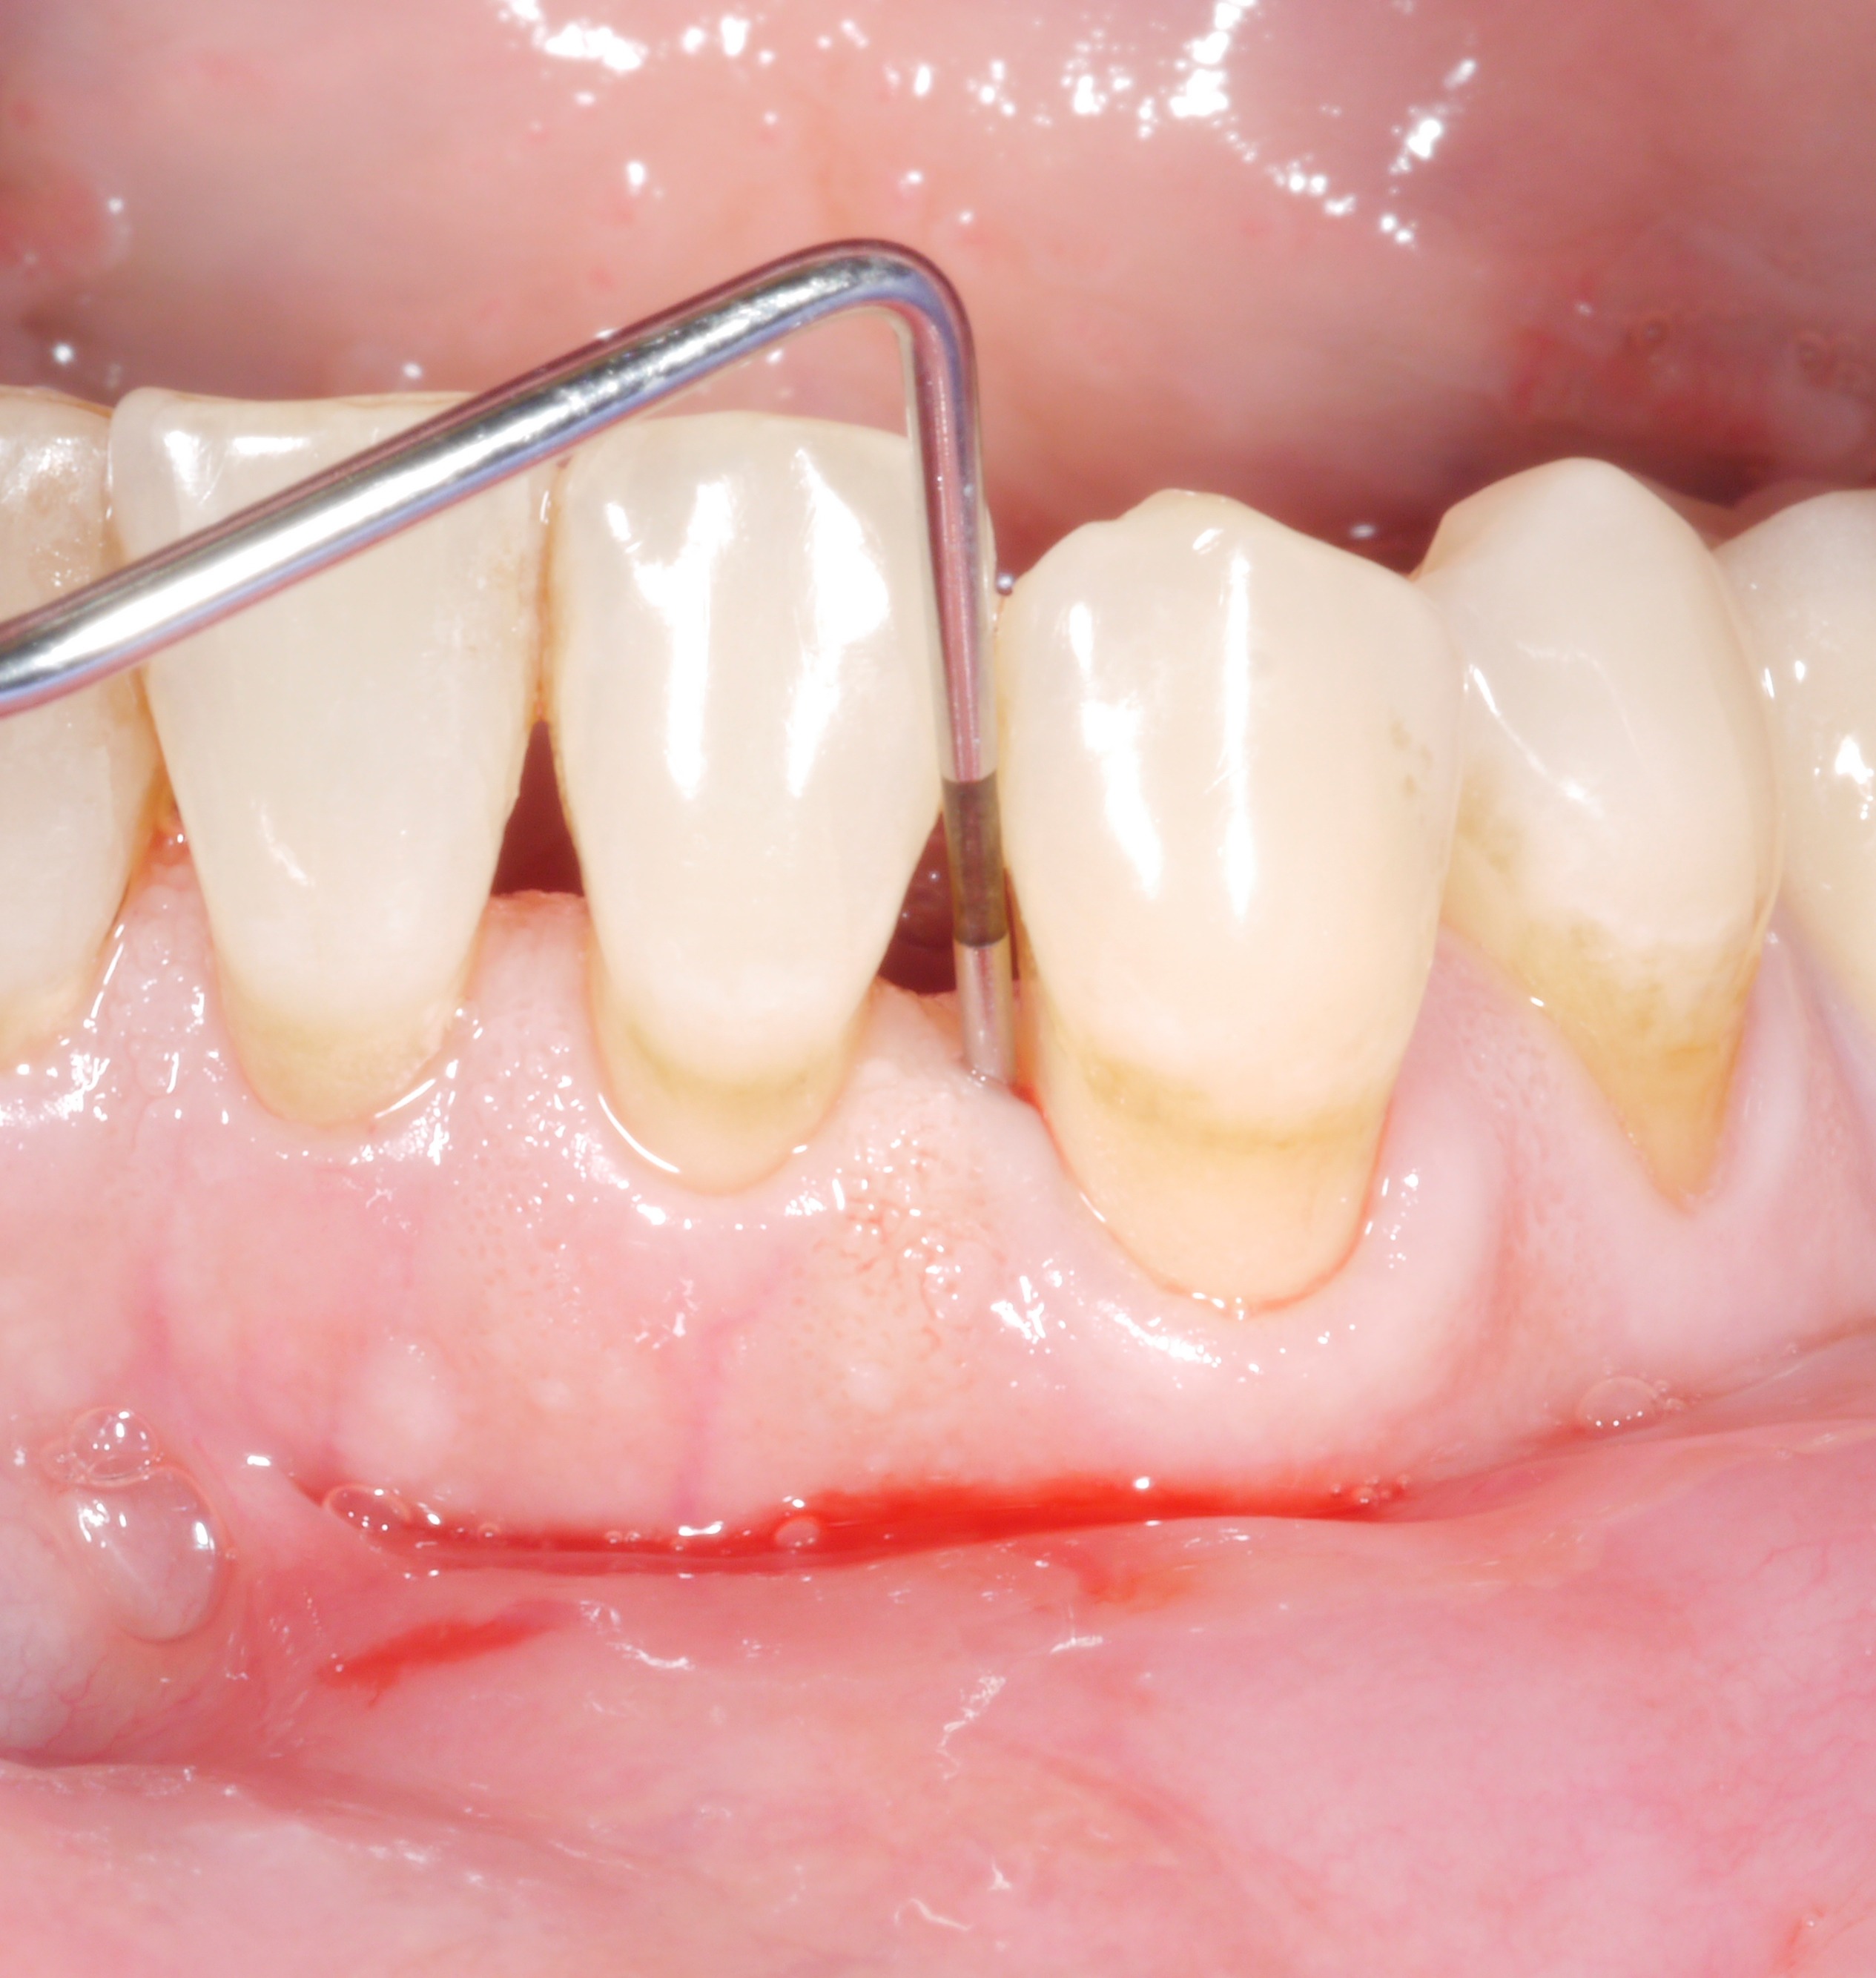

It is a situation we are all too familiar with: following the active phase of treatment, nearly all the patient’s teeth are now unaffected by increased pocket probing depths. However, there are still 1 or 2 places where the treatment goal has unfortunately not been achieved. The following thought might arise: “how bad can it be? A single pocket of 6 or 7 mm – surely that can’t make a big difference?

However, dentists should not rush to say they are content with residual pocket probing depths. This is because even individual residual pocket probing depths of more than 4 mm constitute a problem, as least in the longer term – both for the affected tooth and for the rest of the dentition.

• Bleeding on probing doubled the risk of later tooth loss.

Conclusion: The treatment goal should be to achieve pocket probing depths of 4 mm maximum and an absence of inflammation!